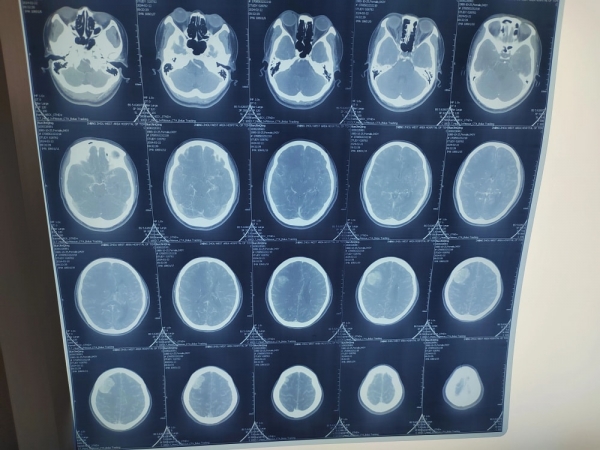

詢問朱大姐情況后,張院長為其進(jìn)行詳細(xì)檢查,CT檢查發(fā)現(xiàn)朱大姐鞍區(qū)瘤體變大,鞍區(qū)是人體大腦顱中窩中央部的位置,得了鞍區(qū)腫瘤會出現(xiàn)“視力降低、頭昏頭痛、內(nèi)分泌異?!钡痊F(xiàn)象,手術(shù)是解決腦部腫瘤的最佳方式。

經(jīng)過檢查發(fā)現(xiàn)孫女士的發(fā)展顱內(nèi)頂葉占位性病變,需要手術(shù)進(jìn)行治療。又是一臺腦瘤手術(shù)?話音未落,張院長立刻說到,做腦科醫(yī)生的走的就是這條路,走,為患者檢查身體,制定方案,跟患者家屬溝通手術(shù)······

手術(shù)的日子依然忙碌,做好充分術(shù)前準(zhǔn)備后,張院長為其右側(cè)頂葉占位性病變切除術(shù),經(jīng)過數(shù)小時的斗爭,孫女士腦部的瘤體全部清除,手術(shù)順利完成。術(shù)后,張院長顧不上吃飯和休息,追隨到病房,觀察孫女士的各項身體體征,叮囑醫(yī)護(hù)各項注意事項后才安心離開,如今孫女士恢復(fù)良好,于近日出院。